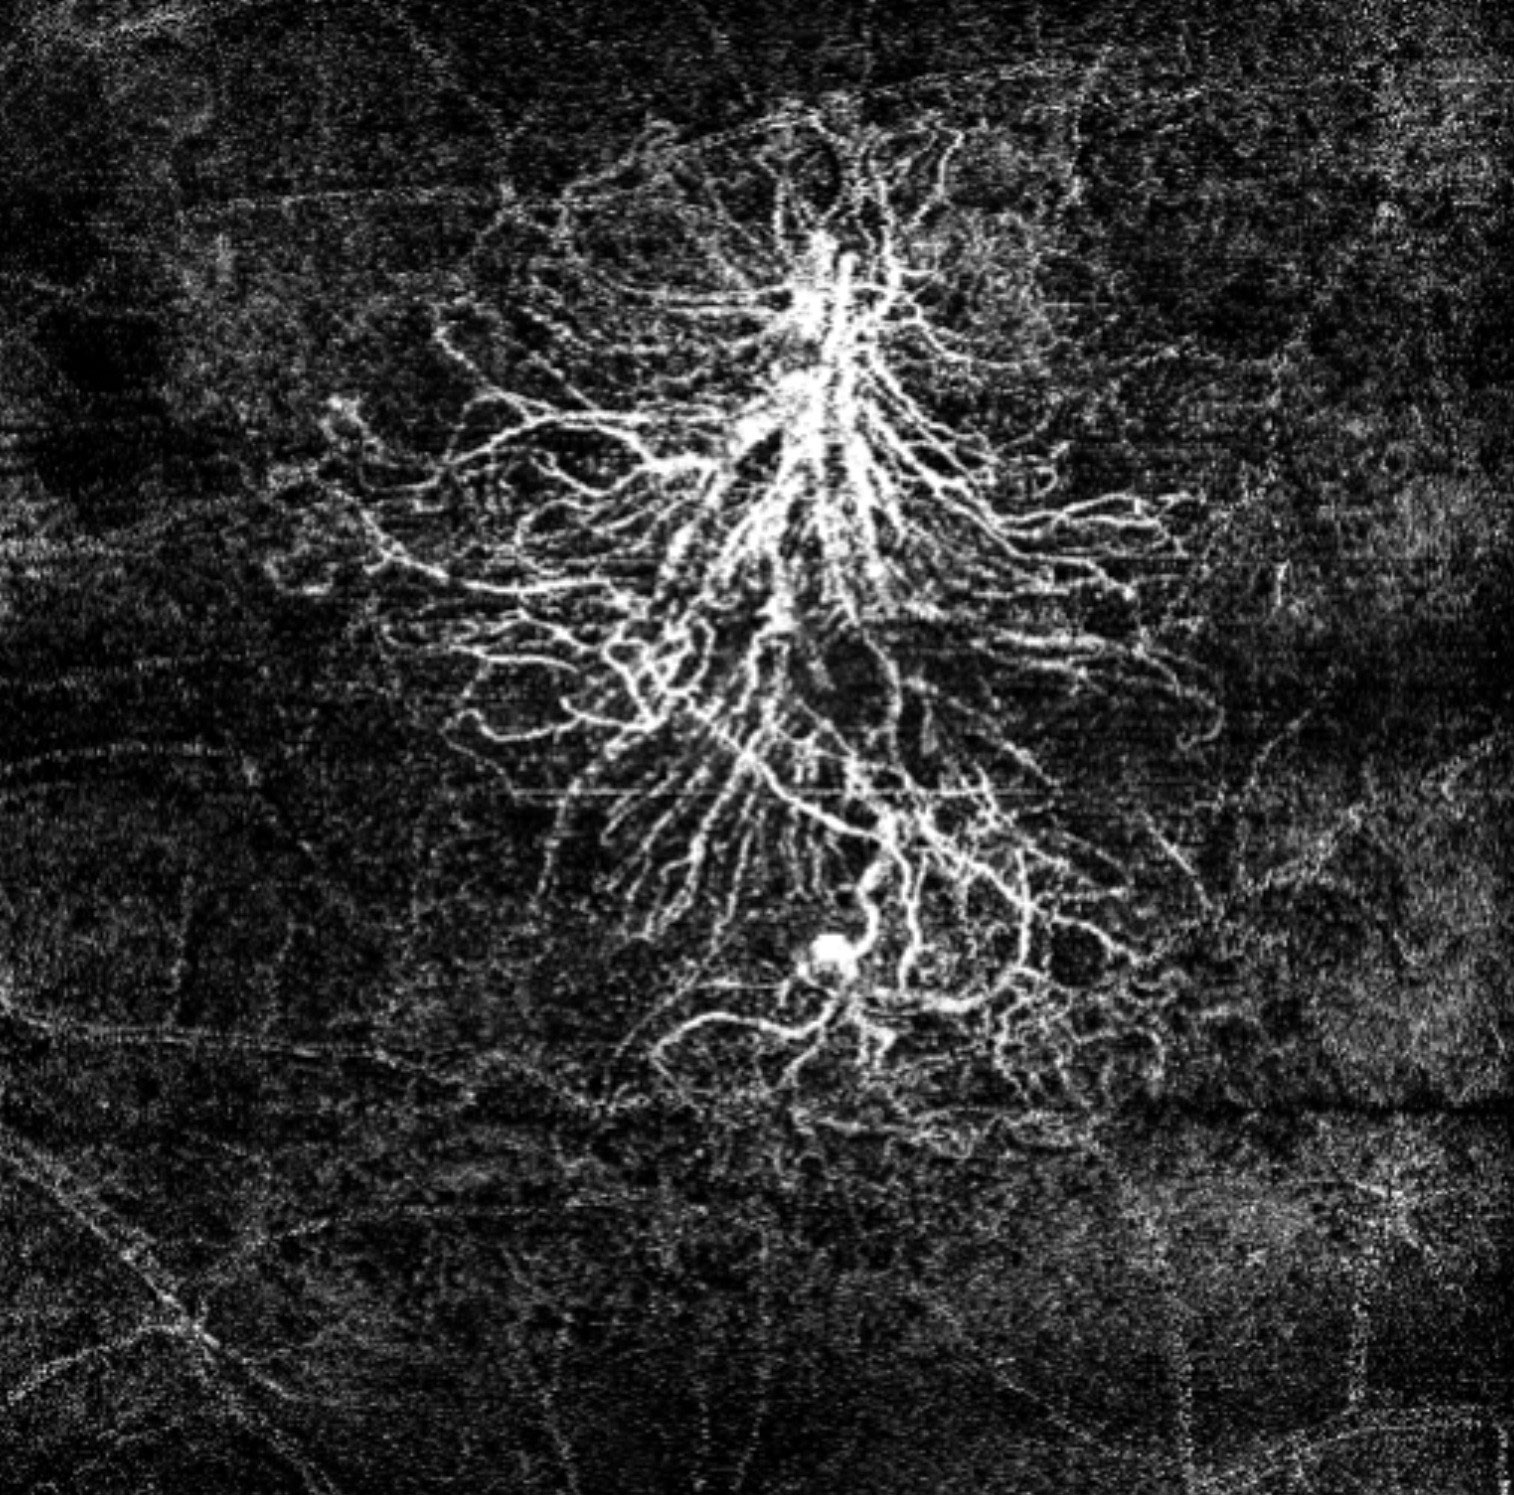

Offering the ideal speed-quality ratio for OCTA, 125 kHz allows you to increase your throughput without any clinically relevant loss in image quality in comparison to the current 85 kHz scan speed. The fast acquisition of images allows for visualization of flow, even in miniscule vessels, while minimizing artefacts, resulting in sharp and detailed images of the capillary network. Additionally, you can decrease chair time when you speed up acquisition with the Glaucoma Module Premium Edition in your glaucoma workflow, if applicable.

125 kHz – A fast scan speed for improved workflow and high OCTA image quality.